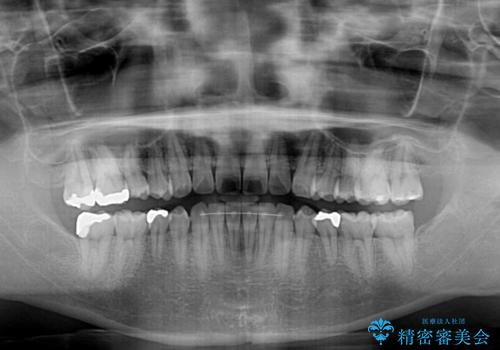

インビザライン・ライトによる矯正治療の後戻り改善

- 矯正治療の後戻りを気にして来院された患者様です。

後戻りは軽微でしたので、インビザライン・ライトにより矯正治療を行うこととしました。

再矯正後の後戻りを防ぐため、歯列排列後に、下顎前歯はワイヤーによる固定を行いました。

下顎前歯の歯列を動かないようにしておくことで、上顎前歯の後戻り防止にも効果を発揮します。